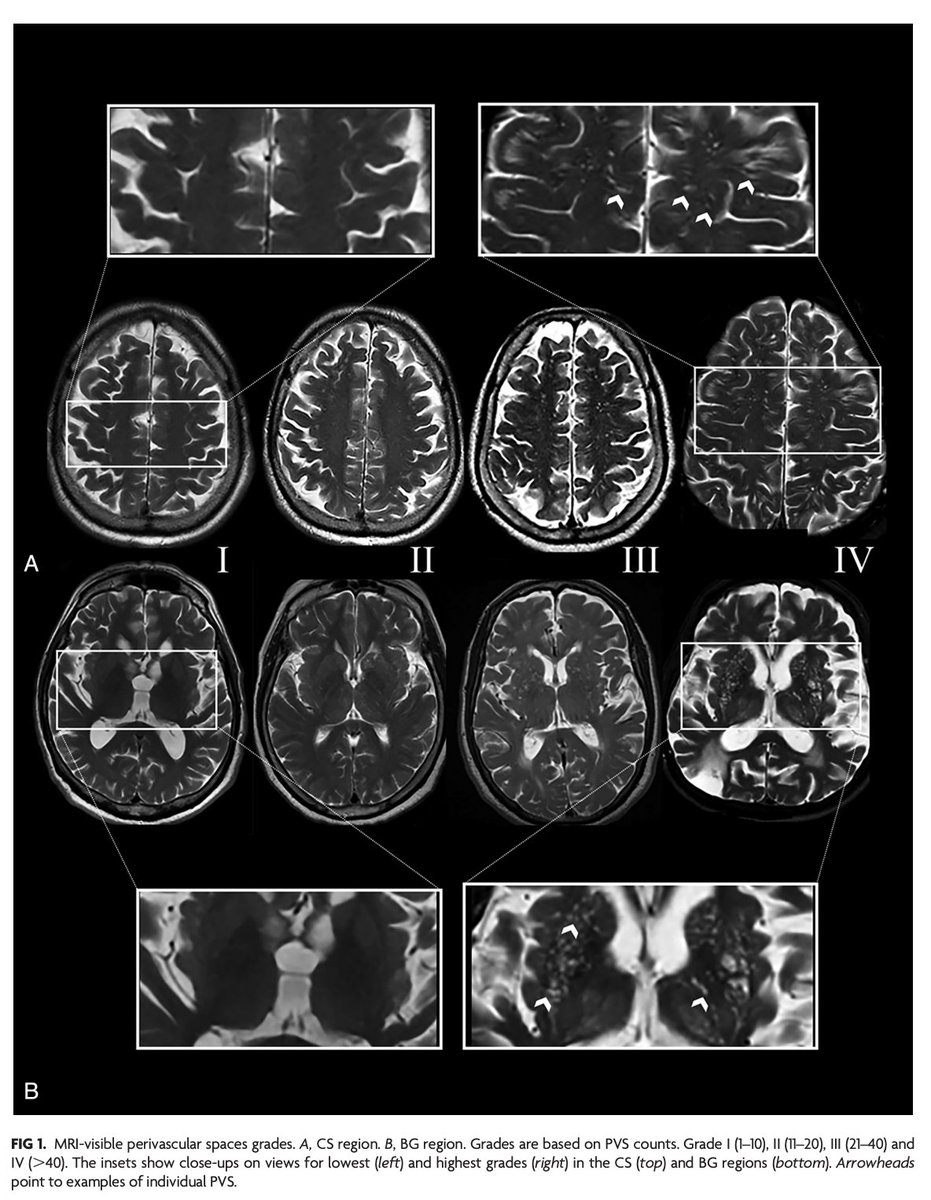

@bmcneurology "Our results indicate that an increased burden of PVS in the CS or the BG is associated with global injury of WM. There also appears to be regional effects of PVS on surrounding WM. The observations noted also would support a role for PVS as early markers of brain injury. "

"Association of MRI-Visible Perivascular Spaces with Early White Matter Injury" https://t.co/QUILpl4wDJ

@bmcneurology

1

6

25